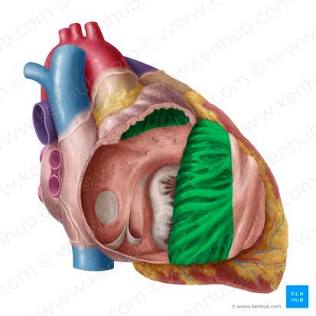

Cardiac Muscle Tissue

Forms most of the wall of the heart, striated, and involuntary.